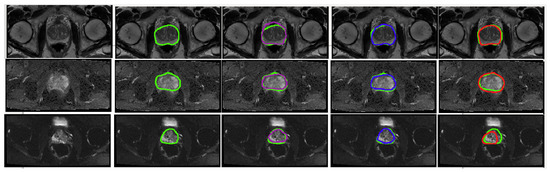

Figure 5.

Visual representation of the predicted segmentation for each model and each modality for a single slice from a case study. From the top row to the bottom: T2W, ADC and DWI. From left to right: Raw test image, Ground truth boundaries in green, U-Net’s prediction in purple, cGAN’s prediction in blue and cycleGAN prediction in red. The quantitative results show the best performance for cGAN followed by U-Net for all evaluation metrics. Scaled images are shown in Figure A1 for better visualisation.

Figure A1.

Visual representation of the predicted segmentation for each model and each modality for a single slice from a case study, where the prostate region is zoomed in and the image brightness is increased. From the top row to the bottom: T2W, ADC and DWI. From left to right: Raw test image, Ground truth boundaries in green, U-Net’s prediction in purple, cGAN’s prediction in blue and cycleGAN prediction in red. The quantitative results show the best performance for cGAN followed by U-Net for all evaluation metrics.